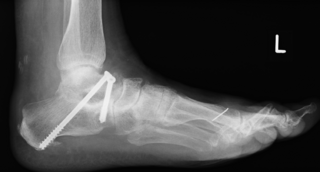

Aufrichtung durch Knochenverschiebung

Die Verschiebung der Ferse nach innen (Calcaneusmedialisierung) führt zur korrekten Lastaufnahme und verbessert die Zugrichtung der Achillessehne. In der Regel sind weitere Maßnahmen wie Verstärkung von Sehnen oder Achskorrektur der Fußinnenseite notwendig. Sollten weitere Beschwerden wie Zehenballen oder Krallenzehen bestehen, wird dieses ebenfalls begradigt.

Aufrichtung durch Stabilisierung

Die Stabilisierung des unteren Sprunggelenkes (Arthrodese) ist eine effektive Methode zur Korrektur des fortgeschrittenen Knick-/Senkfußes, wenn hier bereits als Folge der Fehlstellung Arthrose aufgetreten ist. Dieser Eingriff wird ebenfalls oft mit weiteren Maßnahmen der Fußinnenseite kombiniert. Einige Monate nach der Operation ist in der Regel von außen am Gangbild nicht zu erkennen, dass ein Fußgelenk versteift wurde.

Minimal invasive Fußchirurgie

Die Durchtrennung der Ferse erfolgt über einen kleinen Hautschnitt von ca. 2-3mm. Zur Stabilisierung ist eine Schraube notwendig, die über einen weiteren Schnitt von ca. 7-8mm erfolgt.